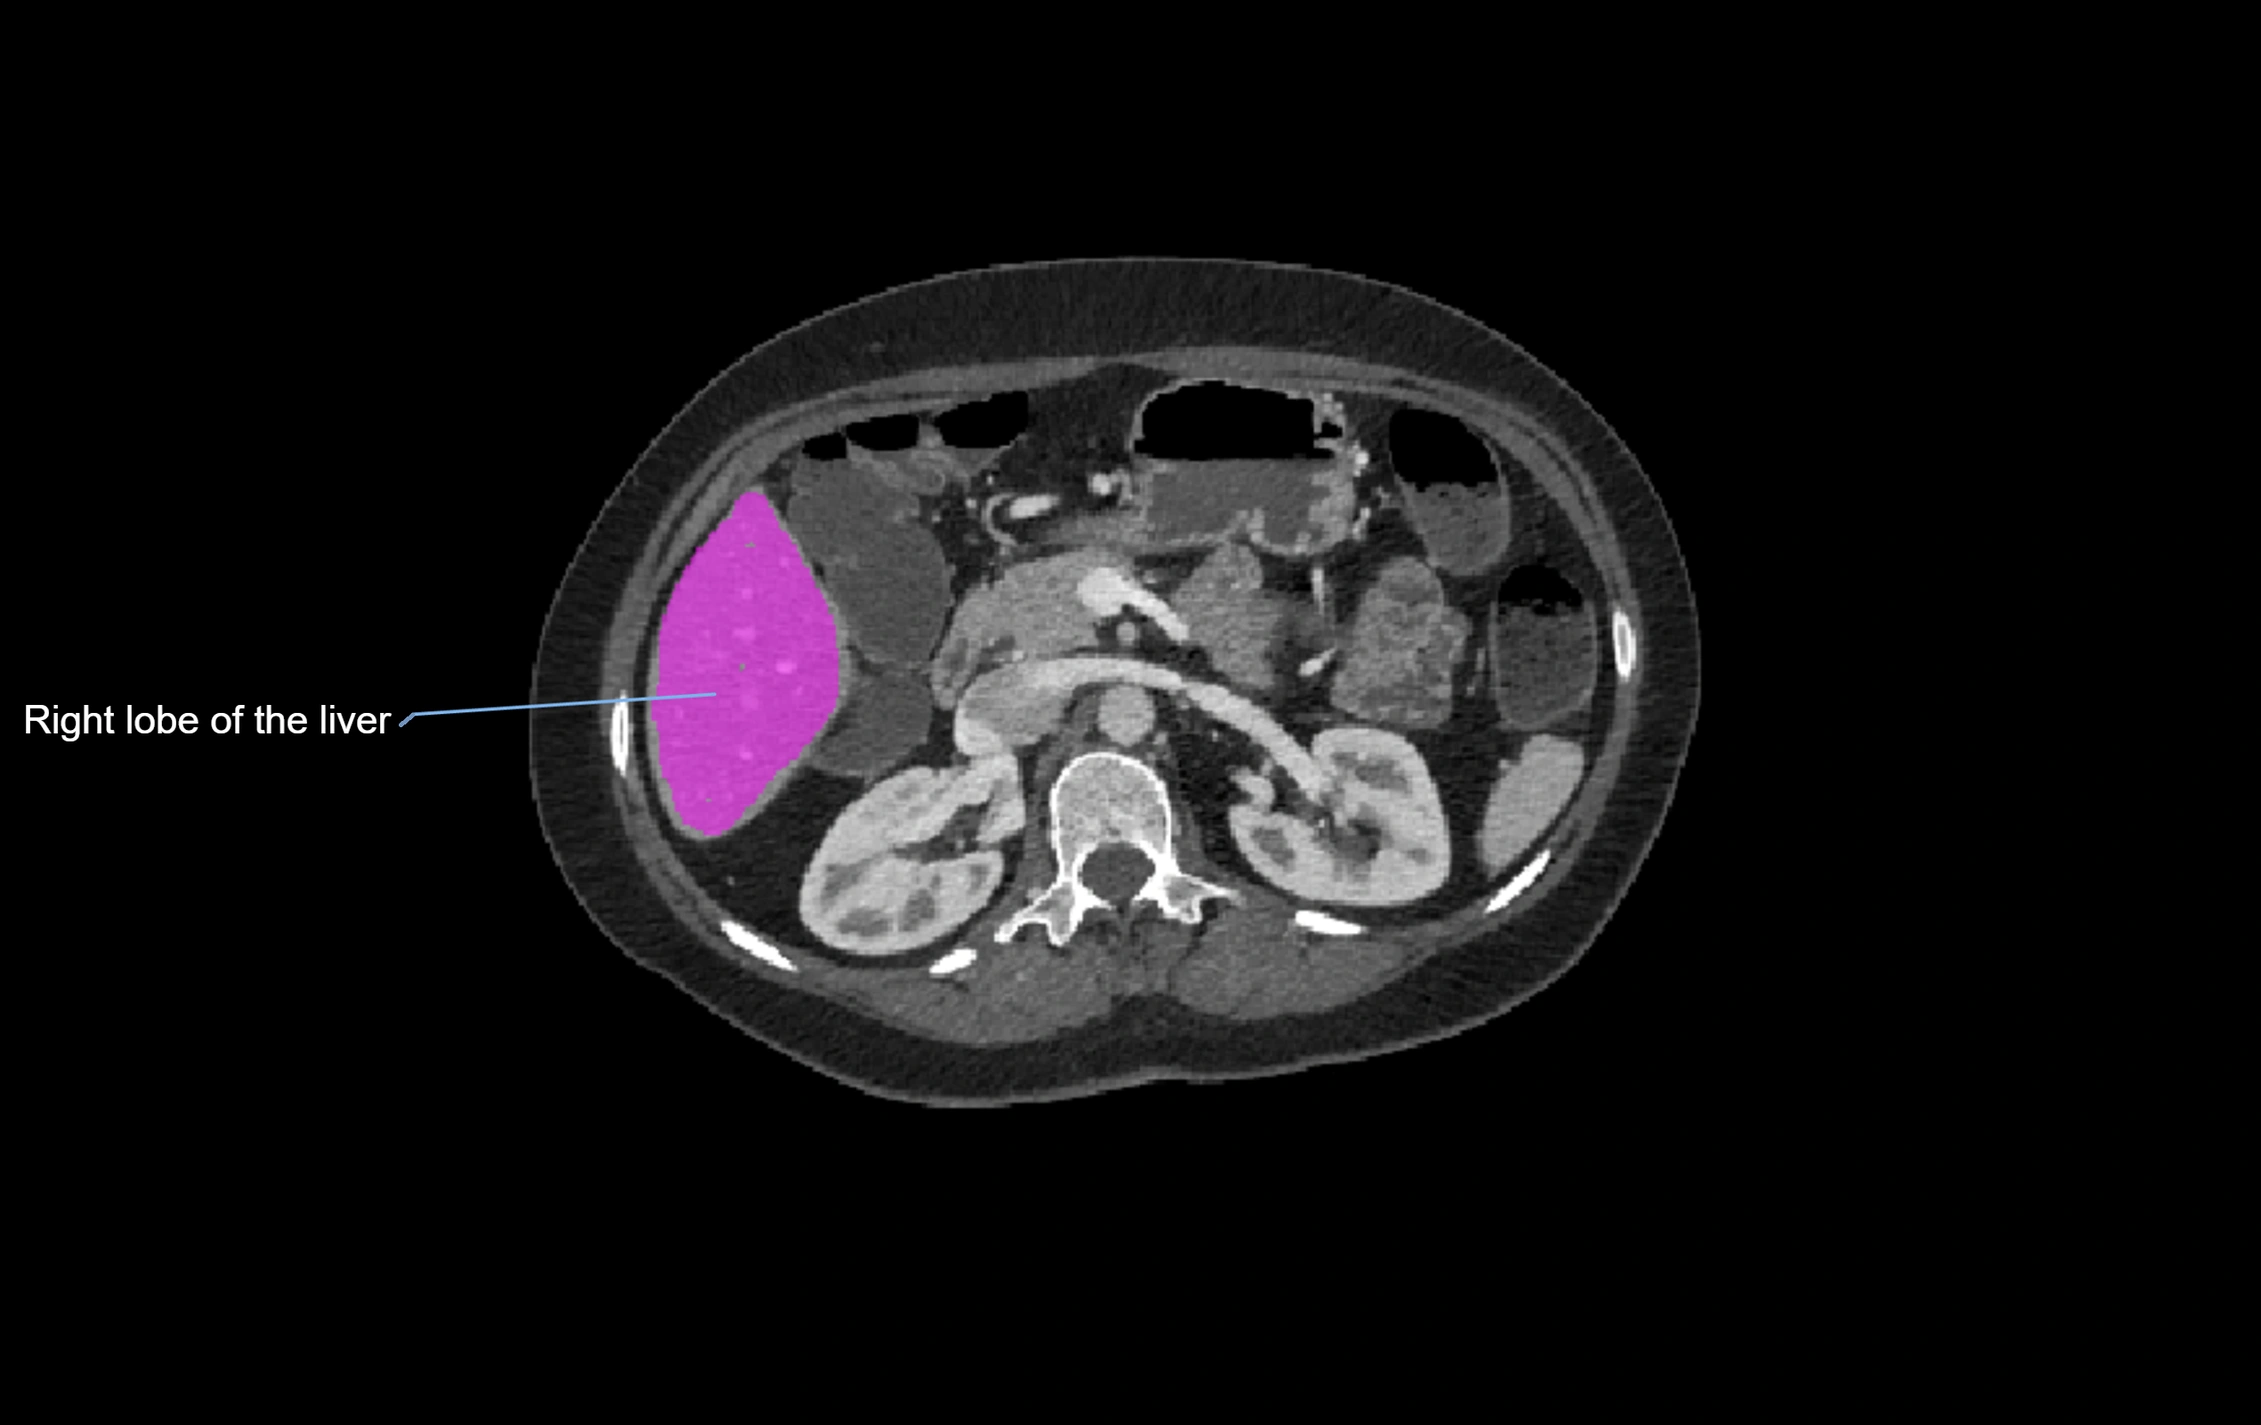

CT Image

image